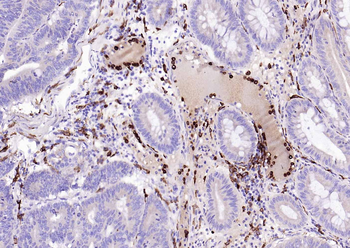

100 μl, 200 μl, 50 μl - LATS2 Rabbit Polyclonal Antibody [orb6306]Featured

IF, IHC-Fr, IHC-P, WB

Human, Mouse, Rat

Bovine, Canine, Equine, Gallus, Rabbit

Rabbit

Polyclonal

Unconjugated

100 μl, 200 μl, 50 μl - Featured